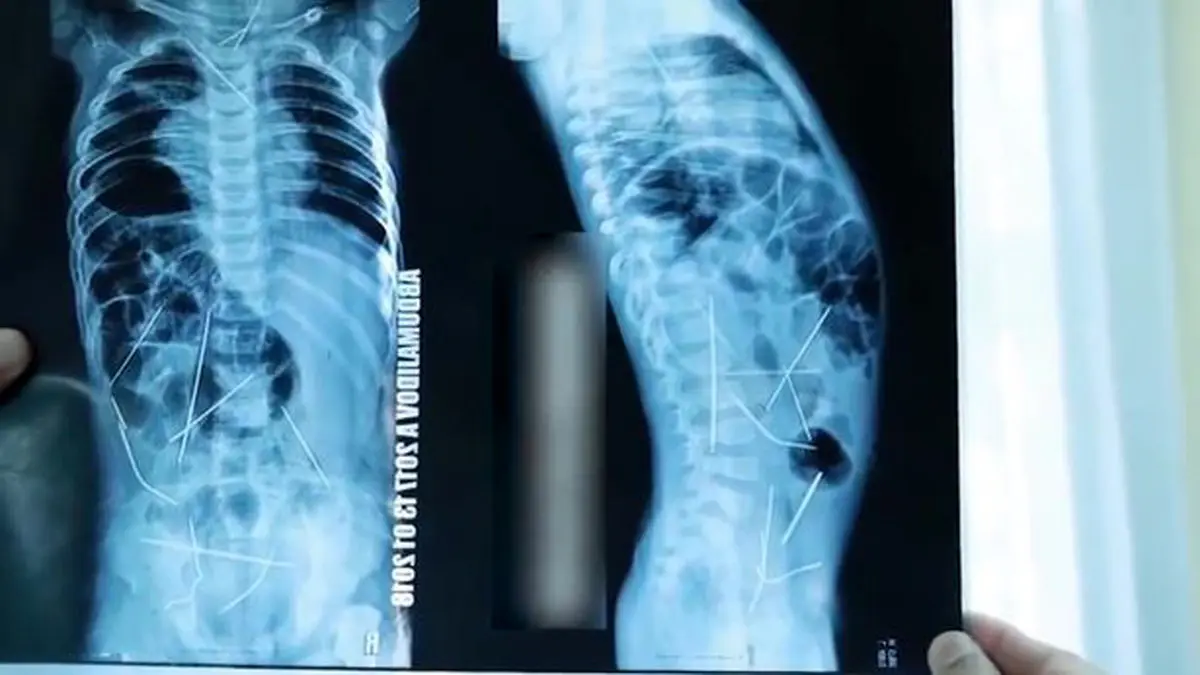

بیرون کشیدن 16 سوزن از بدن کودک 11 ماهه +تصاویر وحشتناک

رکنا: پزشکان ازبکستانی پس از جراحی سنگین و نفسگیر 9 ساعته از بدن کودکی 11 ماهه، 16 سوزن بیرون آوردند که در نقاط مختلف بدنش نفوذ کرده است.

به گفته پزشکان، سوزنها در قلب، گردن، ستون فقرات، روده بزرگ و مثانه کودک فرو رفته بود.

پزشکان برای خارج کردن سوزنها از بدن کودک، 9 ساعت جراحی نفسگیر داشتند.